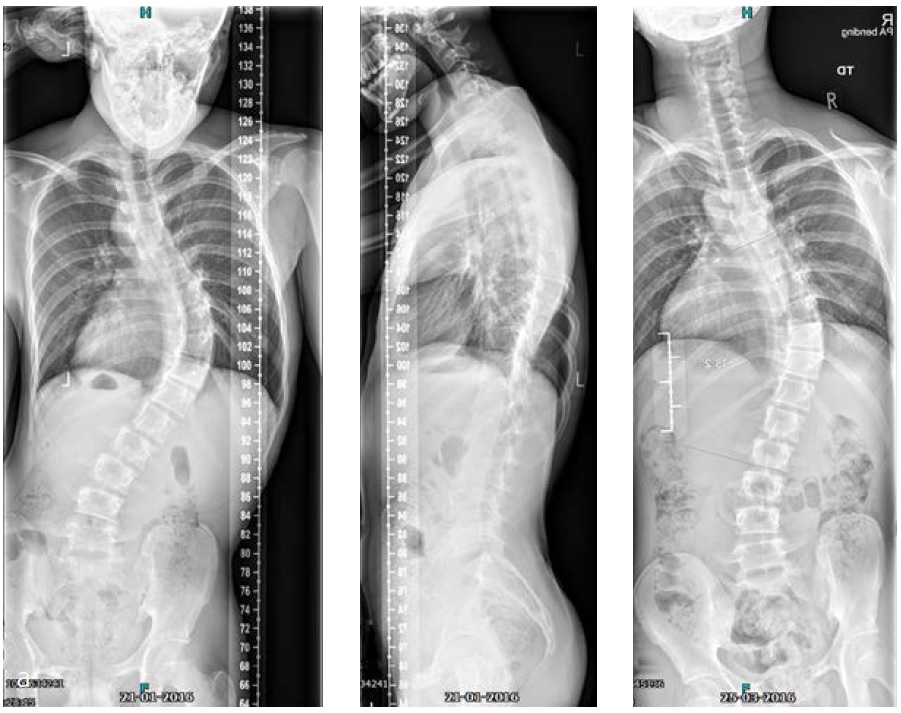

On physical examination a cooperative boy was seen, normal build and height, normal to high paraspinal muscle tone. Standing upright he was off balance to the right. Neurological examination showed absent abdominal skin reflexes bilaterally. The curve was classified as neuromuscular type scoliosis (Fig 6). Due to the curve magnitude, being off balance, and with (severely) limited nonoperative options (Fig 7), surgical treatment was discussed with the family.

He was scheduled for a posterior deformity correction from T4L3. Under general anesthesia, with IONM (TC-MEP) the deformity was corrected. Intraoperatively, an epidural catheter was placed with the tip at T7 for postoperative analgesia.

Mobilisation started the day after surgery. He was discharged the fourth day after surgery. He returned for scheduled follow-up after 7 weeks (Fig 8). He seemed less agitated compared to the period before surgery. He did not seem to have specific limitations.